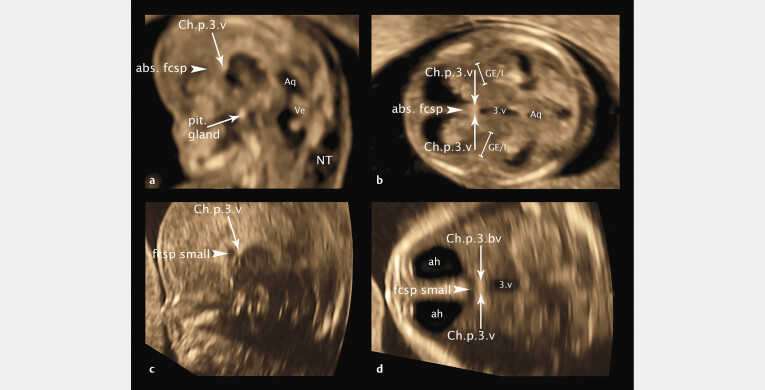

目的探讨高危妊娠冠臀长度为45 ~ 84 mm胎儿的幕上结构——未来透明隔腔、间腔、第三脑室、神经节隆起和丘脑/下丘脑的超声异常。材料和方法本研究回顾性分析了64例胎儿经阴道记录的胎儿脑3D体积,这些胎儿的母亲在GW 12-14期间因胎儿的有机和/或遗传变化向我们的门诊就诊。在这项研究中,我们选择了具有最佳超声质量的胎儿脑3D体积块的胎儿,以便对幕上脑结构进行详细分析和测量,并将结果与遗传分析结果、妊娠后期超声控制和胎儿结局相关联。结果在44例遗传改变胎儿和20例综合征改变胎儿中,27例胎儿发现脑结构改变,并将脑结构与近期发表的妊娠早期12-14周脑结构进行对比分析,首次揭示了早期病理性脑发育的新细节——迁移障碍、轻度前脑畸形(大叶畸形、MIH)、胼胝体发育不全。结论经阴道三维超声可通过直接超声病理分析和病理结果可视化,高质量地检测和分析GW 12-14脑幕上缺损。

Purpose   To detect sonographic abnormalities of the supratentorial structures of the brain - future cavum septum pellucidum, cavum velum interpositum, third ventricle, ganglionic eminence and thalamus/hypothalamus - in fetuses with a crown-rump length of 45-84 mm in high-risk pregnancies. Materials and Methods   This study presents the retrospective analysis of transvaginally recorded 3D volumes of the fetal brain of 64 fetuses whose mothers consulted our ambulatory department for fetomaternal medicine for organic and/or genetic changes of their fetuses at GW 12-14. For this study we selected fetuses with 3D volume blocks of the fetal brain at best sonographic quality enabling detailed analysis and measurement of the supratentorial brain structures to correlate the results with the results of genetic analysis, ultrasound controls in later weeks of pregnancy, and fetal outcome. Results   Of 44 fetuses with genetic changes and 20 fetuses with syndromic changes, structural brain changes were found in 27 fetuses, analyzed by correlating the brain structures with the recently published structures of the brain at gestational week 12-14 in early pregnancy, presenting new details of early pathological brain development - migration disorders, milder variants of holoprosencephaly (lobar, MIH), corpus callosum agenesis, for the first time in early pregnancy. Conclusion   Supratentorial defects of the brain can be detected and analyzed in GW 12-14 in detail by direct analysis of sonopathology and visualization of pathological measurements using transvaginal 3D sonography in high quality.